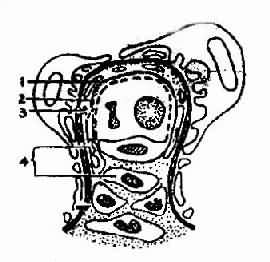

1.微小病变型肾病光镜下肾小球结构基本正常或仅有轻微病变(上皮细胞肿胀、空泡、变性、系膜组织轻度局灶性增生),近端肾小管上皮细胞轻重不等的脂肪变性,所以亦称类脂性肾病。电镜下观察可见肾小球上皮细胞有严重的足突融合现象,故亦称足突型肾病(Foot Process nephrosis)(图4-2-2)。附正常肾小球毛细血管袢模式图(图4-2-1)。

图4-2-1正常肾小球毛细血管袢模式图

1、上皮细胞 2、基底膜 3、红细胞 4.内皮细胞5、足突 6、系膜基质7、系膜细胞

图4-2-2 肾小球微小病变模式图

上皮细胞足突融合

荧光检查阴性。该型病变的临床表现以肾病综合征Ⅰ型为主。